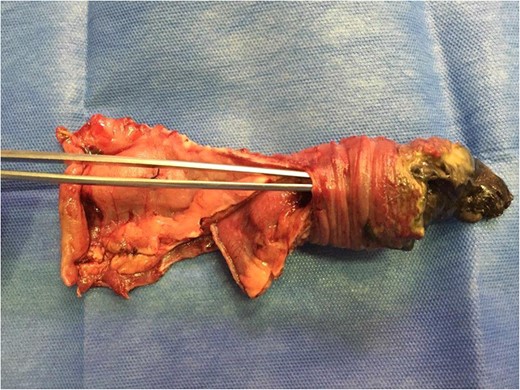

Not managing to reduce the invagination using blunt manual techniques, we performed a mini-laparotomy. Once the enterotomy was done and the invaginated segment was reduced, we observed necrotic intussuscepted mucosa, performing a resection and termino-terminal jejunojejunal anastomosis at 4 cm from the foot of the Roux-in-Y (Fig. 2). Upon finalizing the procedure, we once again confirmed fetal vitality (FCF: 140 bpm).

The dissection tweezers show the invaginated bowel segment. On the far right, an area of necrosis is seen with fibrine greenish streaks.

The surgical treatment alternatives (Table 1) consist in the reduction [1], reduction plus resection or IR (intestinal resection) plus EEA0 [5, 9]. In our case, the IR plus EEA decision was made because of the necrosis of the intussuscepted block.